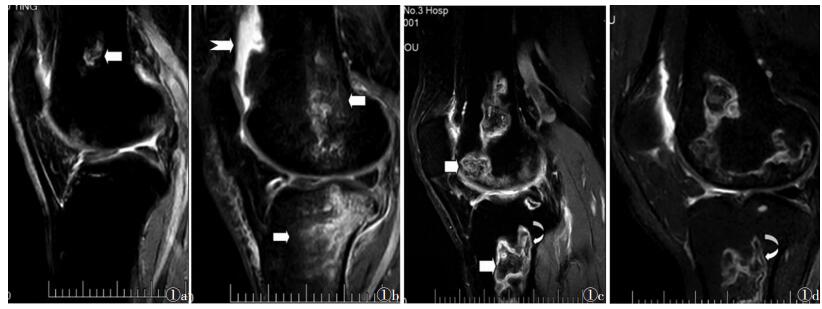

2 结果 2.1 影像表现16例均双侧对称性发病,双侧髋关节、肩关节未见异常改变。16例均出现双侧股骨下段、胫骨上段多发的、类椭圆形、边界清楚的、地图板块样病变,病灶内部T1WI低信号、T2WI高信号,病灶边界呈线样T1WI低信号、T2WI低信号(图 1a)。6例(37.5%)在追踪观察中出现骨髓腔斑片样T1WI低信号、T2WI高信号(图 1b)。3例(18.8%)出现关节腔积液。9例(56.2%)出现双边征:病灶边界T1WI呈低信号,T2WI见内高外低双线平行迂曲走行信号(图 1c,1d)。

| 图 1 男,41岁,HIV感染3年,高效联合抗逆转录病毒疗法(HAART)治疗9个月,右膝关节矢状位FSE T2WI示股骨下段孤立类椭圆形T2WI高信号的骨梗死病灶(白箭),边界清楚,呈线样低信号 图 1b HAART治疗12个月,右膝关节矢状位T2WI STIR示股骨下段、胫骨上段骨髓腔出现斑片样水肿高信号(白箭),骨梗死病灶边界显示不清,见关节腔积液(燕尾箭) 图 1c HAART治疗18个月,右膝关节矢状位FSE T2WI示股骨下段、胫骨上段出现地图板块样骨梗死病灶,病灶范围扩大、数目增多(白箭),骨水肿减轻,见双边征(弧形箭) 图 1d HAART治疗24个月,右膝关节矢状位FSE T2WI,骨梗死病灶病灶境界清楚,内部信号减低,见双边征(弧形箭) |

16例随着HAART治疗时间的延长,骨梗死病灶数目进行性增多,病灶面积进行性扩大(图 1c,1d)。